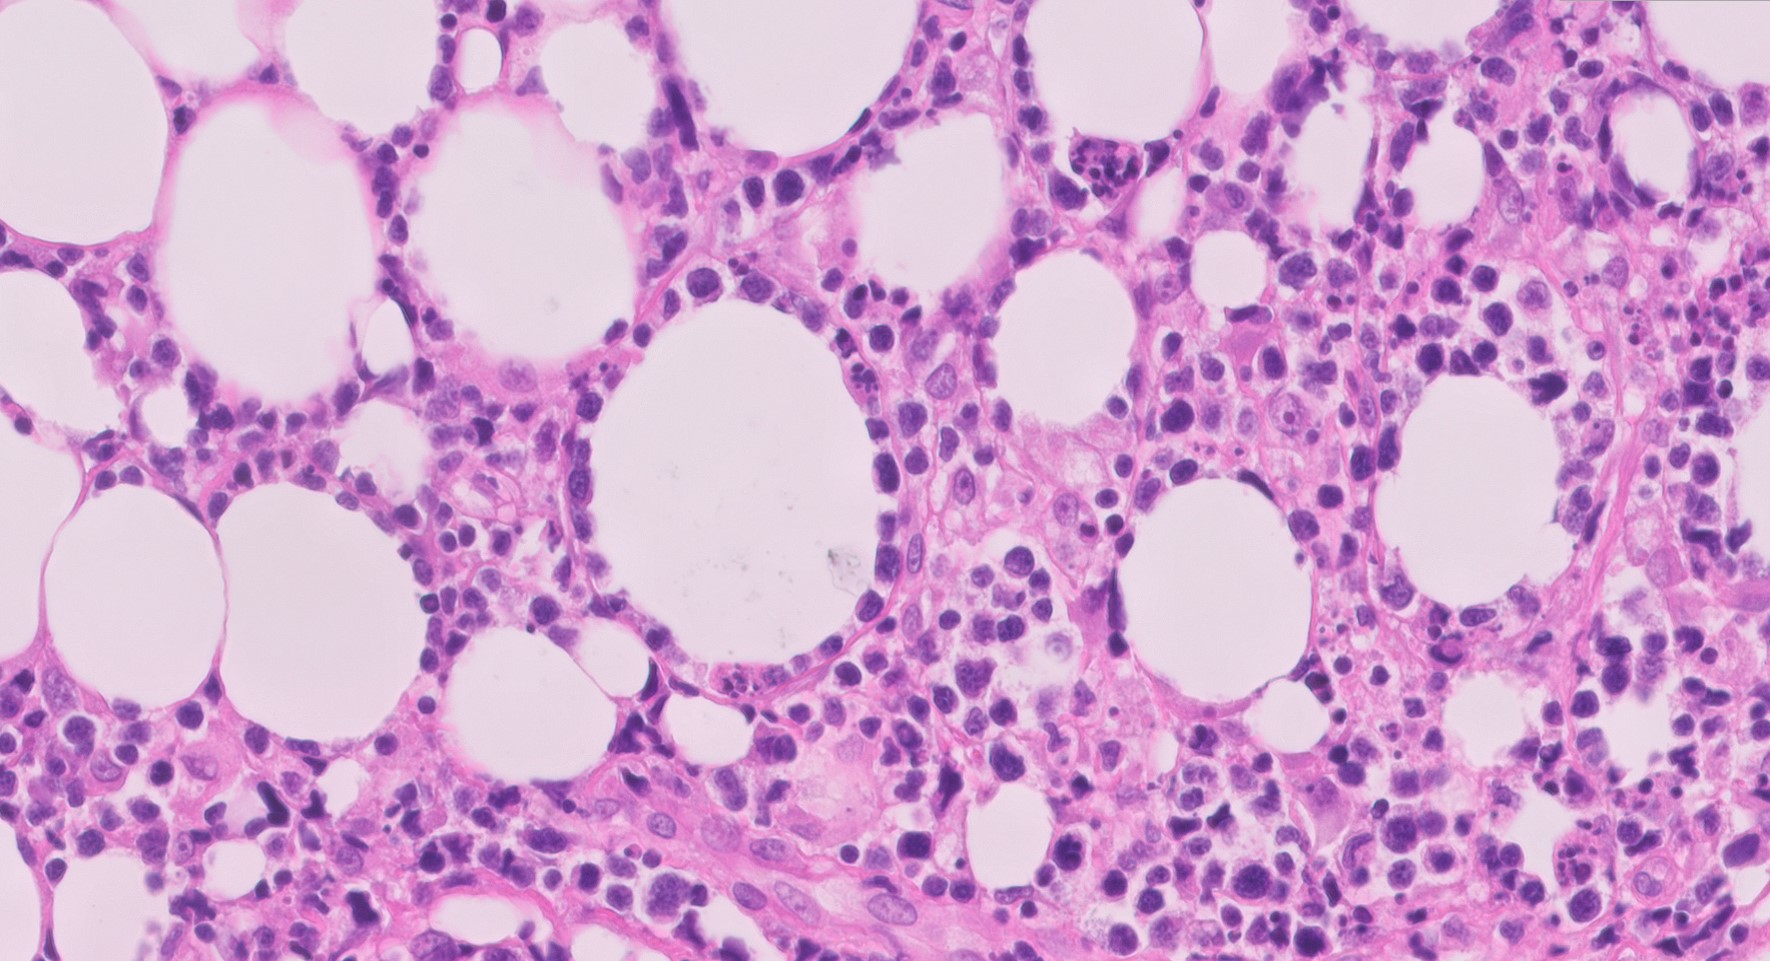

PA subcutaneous panniculitis-like T-cell lymphoma PA subcutaneous panniculitis-like T-cell lymphoma

histologisch beeld histologisch beeld

PA-foto's: dr. E.J. Kooi, patholoog, Afdeling Pathologie, Amsterdam UMC.